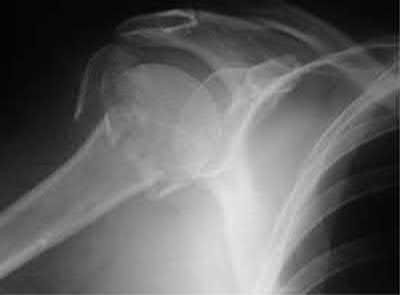

A 44-year-old male is struck by a vehicle while riding his bike. In the trauma bay, he complains of right shoulder pain . Upper extremity physical exam reveals no neurologic deficits, and an initial radiograph of the shoulder is shown in Figure A. A CT scan of the shoulder shows 1cm of posterior displacement of the tuberosity fragment. Which of the following is true regarding this injury?

The radiograph in Figure A demonstrates a posteriorly displaced greater tuberosity fracture. These injuries are often associated with anterior shoulder dislocations, and concomitant rotator cuff tears. The subscapularis attaches to the lesser tuberosity, and is not a deforming force. Open reduction and internal fixation (ORIF) is usually the treatment of choice, and it is well accepted that more than 5mm of displacement is an indication for surgery in patients that require overhead function of the arm.

Flatow et al evaluated 12 patients who were an average of five years status post ORIF of displaced greater tuberosity fractures. All fractures healed without postoperative displacement. Six patients had an excellent result and six had a good result.

Platzer et al retrospectively analyzed functional and radiographic results of 52 patients with operative treatment of displaced greater tuberosity fractures at an average time of 5.5 years from surgery compared to 9 patients with equivalent injuries treated non-operatively. Evaluation of the results of the surgical study group and the nonoperative control group, patients with reduction and fixat ion of greater tuberosity fractures had significantly better

results on shoulder function than did those with conservative treatment.